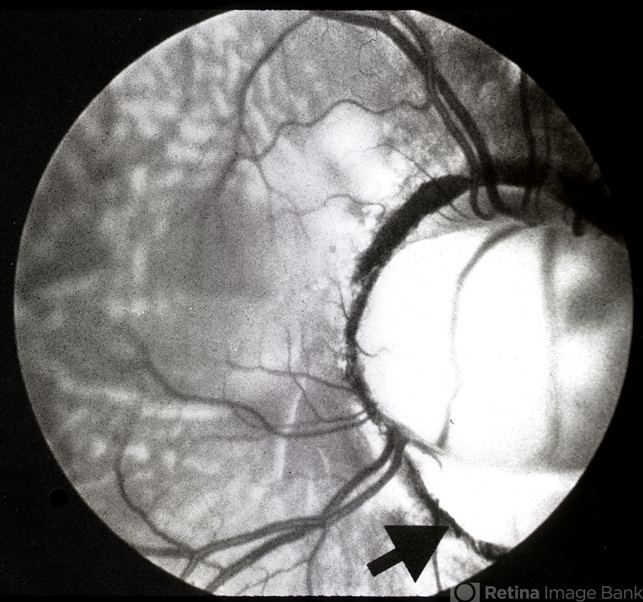

- optic nerve coloboma

- 21-year-old.